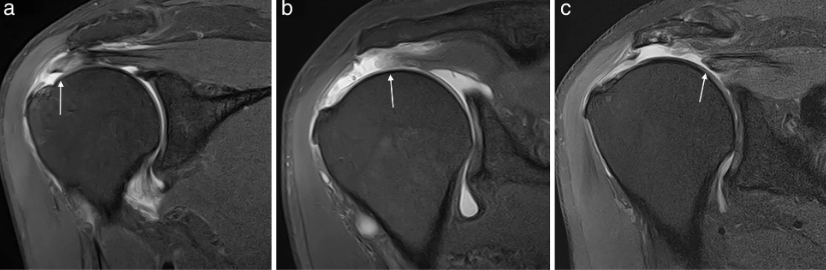

5. Diagnóstico

O diagnóstico de uma lesão do manguito rotador geralmente inclui uma avaliação clínica, testes de força e movimento, além de exames de imagem como:-

- Ultrassonografia: útil para identificar inflamação ou rupturas parciais.

- Ressonância Magnética (RM): pode detectar lesões mais detalhadas, como rupturas completas ou degeneração dos tendões.